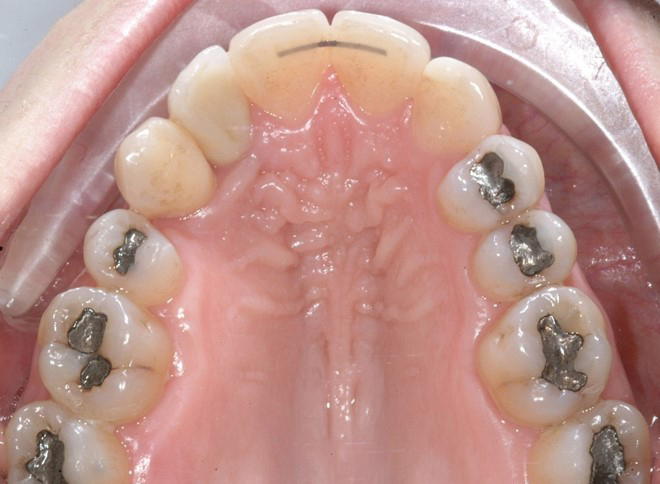

La rifinitura del caso ha previsto il completamento del livellamento del piano occlusale posteriore inferiore mediante meccanica cross-over con sezionali in acciaio .017”x .025” applicati sui primi e secondi molari e catenelle di derotazione tra i centrali superiori e tra 1.6 e 1.5 (Figure 8a-b).

Al termine del trattamento ortodontico, che ha richiesto 24 mesi di terapia, è stata applicata una contenzione fissa3 all’arcata inferiore mediante filo multi-intrecciato coassiale .0195” esteso da 4.4 a 3.5 al fine non solo di stabilizzare il risultato sia sul piano orizzontale sia verticale, ma soprattutto per prevenire adeguatamente l’affollamento dentale terziario (Figure 9a-e).

All’arcata superiore è stato mantenuto il pontic in composito in sede 1.2, poiché la paziente, per esigenze personali, aveva preferito rimandare a un tempo successivo la sostituzione implantare di 1.2 agenesico, così come la coronoplastica definitiva di 2.3.